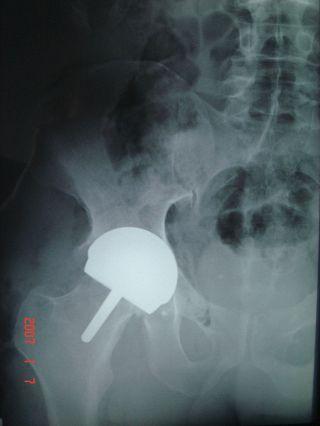

At AEA I found that they had progressed as well. They now regularly brought in an orthopedist from Hong Kong to serve the Beijing community, and it turned out Dr. Jason Brockwell specializes in hip resurfacing surgery. It took about 3 weeks for me to get in to see him, and after that about 90 seconds for him to recognize that I was the ideal candidate for this surgery: active adult with severe hip degeneration. He explained to me that with resurfacing there were no limits on the sports I could do, except perhaps bungee jumping. (One former patient now does full contact karate.) And, since the technology was only 10 years old they could not say for sure, but experience indicates this may be a lifetime fix: most people will not need any replacements.

That sure sounded good to me, so as soon as my insurance company agreed I set up a date with Doctor Brockwell: December 29, 2006.

I had my annual checkup a couple weeks ago. The doctor was very pleased, and said that not only could I continue my activities, but that as far as he could tell I have the hip for life.

The other thing is more an inconvenience. The leg has been a little sore for a while: achy when I sit for long periods, requiring a day or two's rest after activity like ultimate - in fact, very much like before the operation. I was a little worried that it could be the hip failing, but didn't even have a chance to ask Dr. Brockwell. As I went on to see him he was looking at the x-ray, and said, "I see you have dug yourself a divot." Apparently I am flexing the leg more than the plan called for, and the metal head is digging into the thigh bone. This is putting a dent in the bone - nothing to worry about, the doctor says, but it will be a little sore until the process is finished. No problem, as long as I know it is not damaging, it isn't hurting enough to stop me from doing anything.